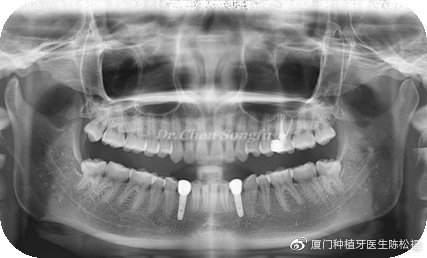

治疗效果:前后对比图片

案例总结:

1、正畸治疗开辟了合适的修复空间的同时,纠正了前牙不良的覆合关系。

2、良好的种植设计与种植修复恢复了可靠的修复效果。